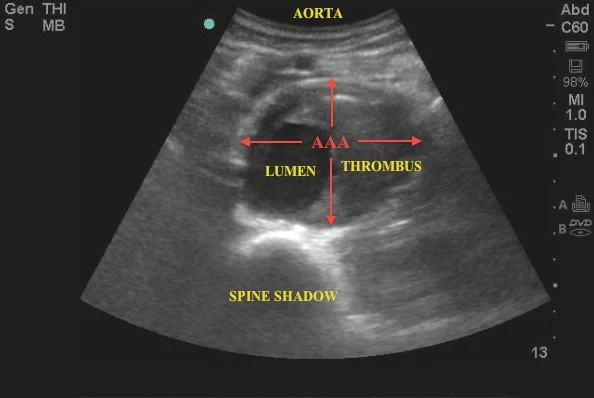

• Abdominal Aorta Sonography